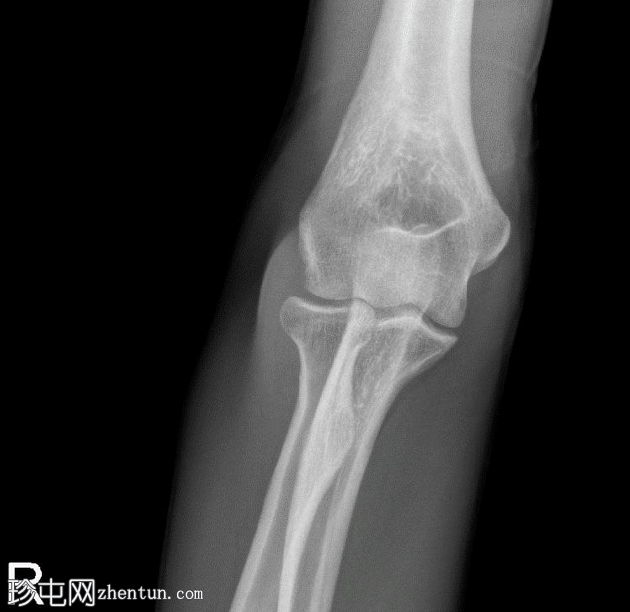

3.png

正位片

桡骨头关节内粉碎性骨折,关节面轻微凹陷。肱骨远端前侧可见移位的骨碎片,桡骨头位片上清晰可见。可见前后脂肪垫征,提示肘关节积液。

未见肘关节脱位,肱桡骨小头排列保持正常。冠突水平可见复合阴影,可能与软组织重叠或投影伪影有关。桡骨和尺骨骨干外观完整,无骨折征。周围软组织肿胀。